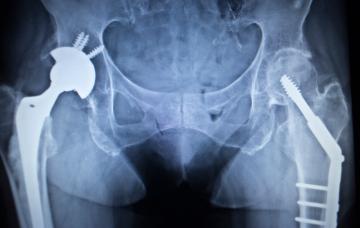

Tratamiento de la osteonecrosis

El tratamiento para la osteonecrosis más eficaz, si se establece la necrosis del hueso o de la articulación, será la sustitución quirúrgica por una prótesis.